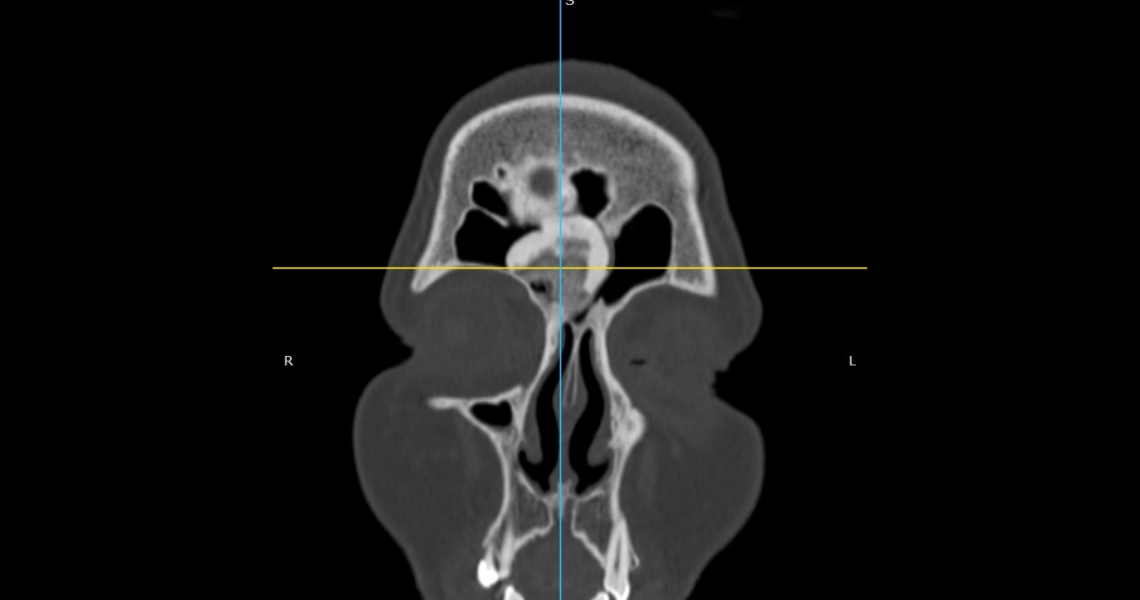

У ЛОР-відділенні КП «Полтавська обласна клінічна лікарня ім. М.В. Скліфосовського» було вперше видалено остеому лобної пазухи гігантських розмірів ендоназальним доступом.

For the first time, a giant frontal sinus osteoma was removed endonasally in the ENT Department of the Municipal Enterprise “M. V. Sklifosovsky Poltava Regional Clinical Hospital.”